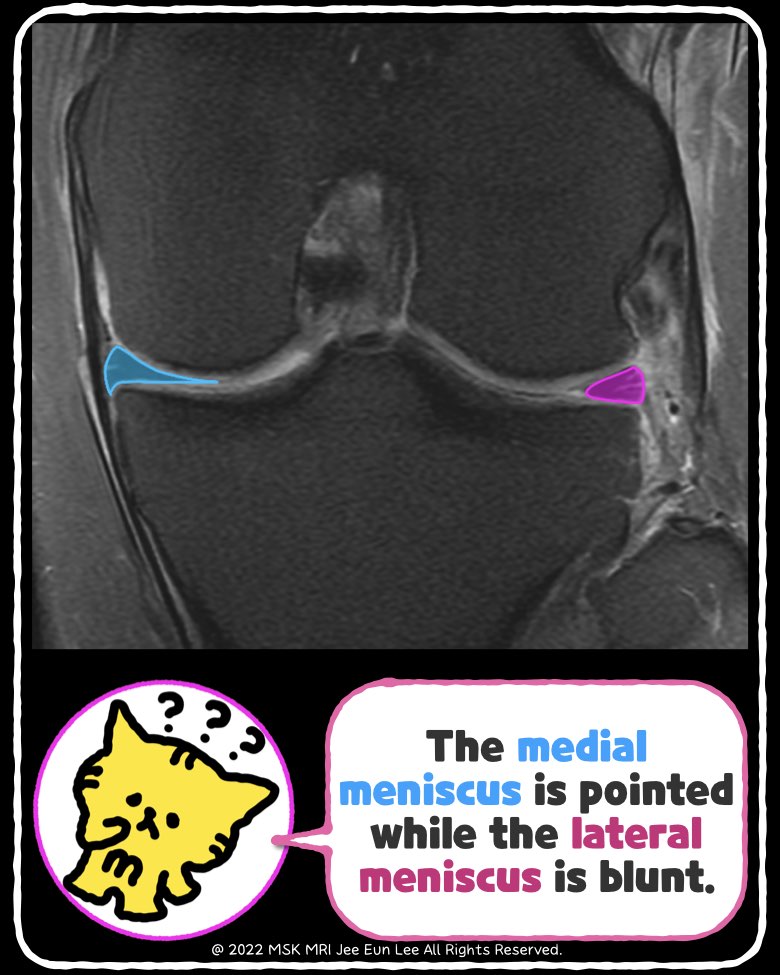

๐น Clues for Diagnosis: Look for a Blunted Meniscus

- In cases without prior surgery, a blunted lateral meniscus on MRI should raise suspicion.